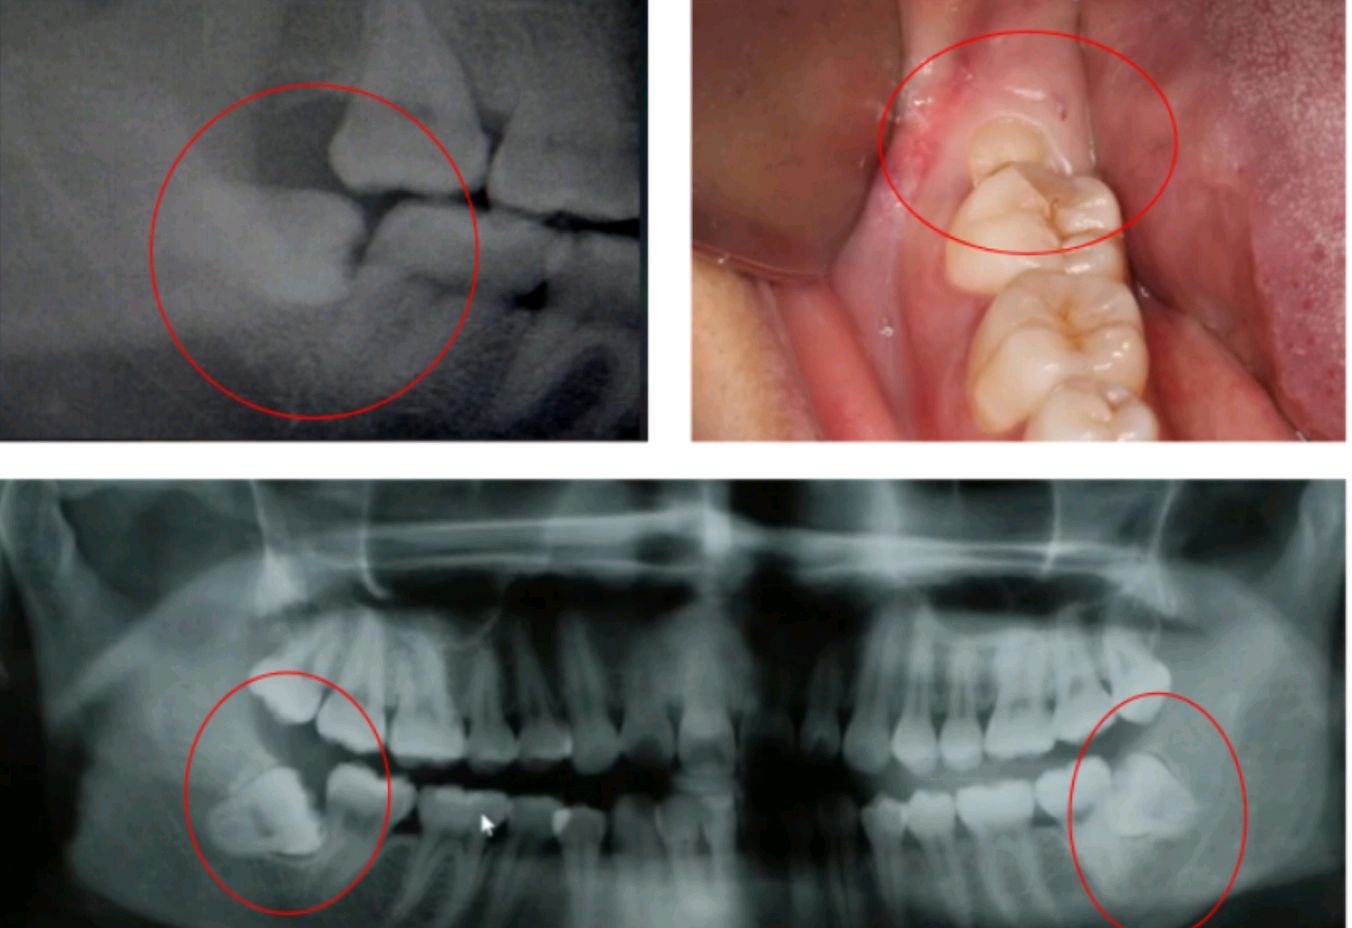

举例的图示智齿都要建议及早拔除